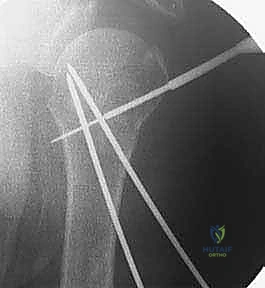

4. إدخال الأسلاك المعدنية (K-wires)

بمجرد أن يصبح الكسر في الوضع المثالي، يتم إدخال أسلاك كيرشنر (Kirschner wires) الدقيقة عبر الجلد مباشرة إلى العظم. يتم توجيه هذه الأسلاك بزوايا هندسية مدروسة لضمان أقصى درجات الثبات. عادة ما يتم استخدام 2 إلى 4 أسلاك.

5. التحقق من الثبات وقص الأسلاك

بعد وضع الأسلاك، يتم تحريك الكتف بحذر للتأكد من ثبات الكسر التام. بعد ذلك، تُقص نهايات الأسلاك وتُترك بارزة قليلاً فوق الجلد (أو تُدفن تحت الجلد مباشرة) لتسهيل إزالتها لاحقاً.

6. التقييم النهائي والإغلاق

تُؤخذ صور شعاعية نهائية لتوثيق نجاح العملية، وتُغطى مواقع دخول الأسلاك بضمادات معقمة.

صور إضافية من داخل غرفة العمليات توضح دقة الإجراء: